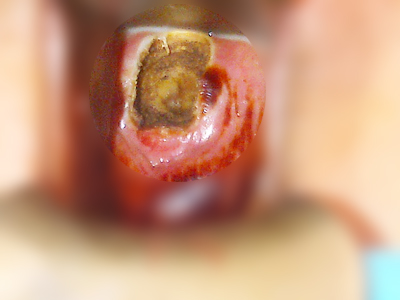

Cratère après l'electroconisation

Il existe plusieurs techniques de conisation. Le choix de la technique appartient au chirurgien. Il dépend principalement de l’étendue des lésions et de l’expérience du chirurgien. Les techniques les plus courantes sont la conisation à l’anse diathermique (ECAD : éléctro conisation à l'anse diathermique ; bistouri électrique), au bistouri froid (bistouri normal) ou au laser.